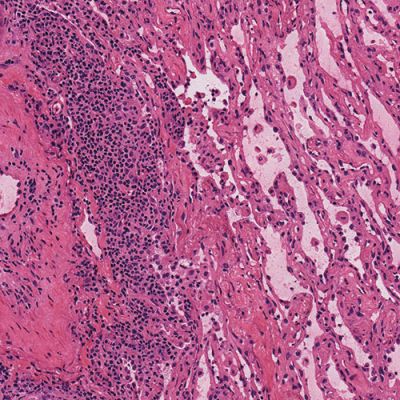

Pathologists rely heavily on the frozen section technique for intra-operative consultation when the surgeon requires a rapid diagnosis or immediate feedback regarding surgical margins. Frozen sections offer a short turnaround time (15-20 minutes) but usually have the disadvantage of lower diagnostic quality than paraffin sections due to cryoembedding artifacts and variability in staining protocols.

Milestone offers a new approach to overcome these limitations by combining the artifact-free freezing process of PrestoCHILL with the superior processing and staining capabilities of PRESTO PRO.

The advantage of PRESTO PRO is that it provides a standardized and reproducible process that is capable of both efficient processing and staining protocols. This results in improved morphology of the analyzed specimens and maintains a high standard of result quality.